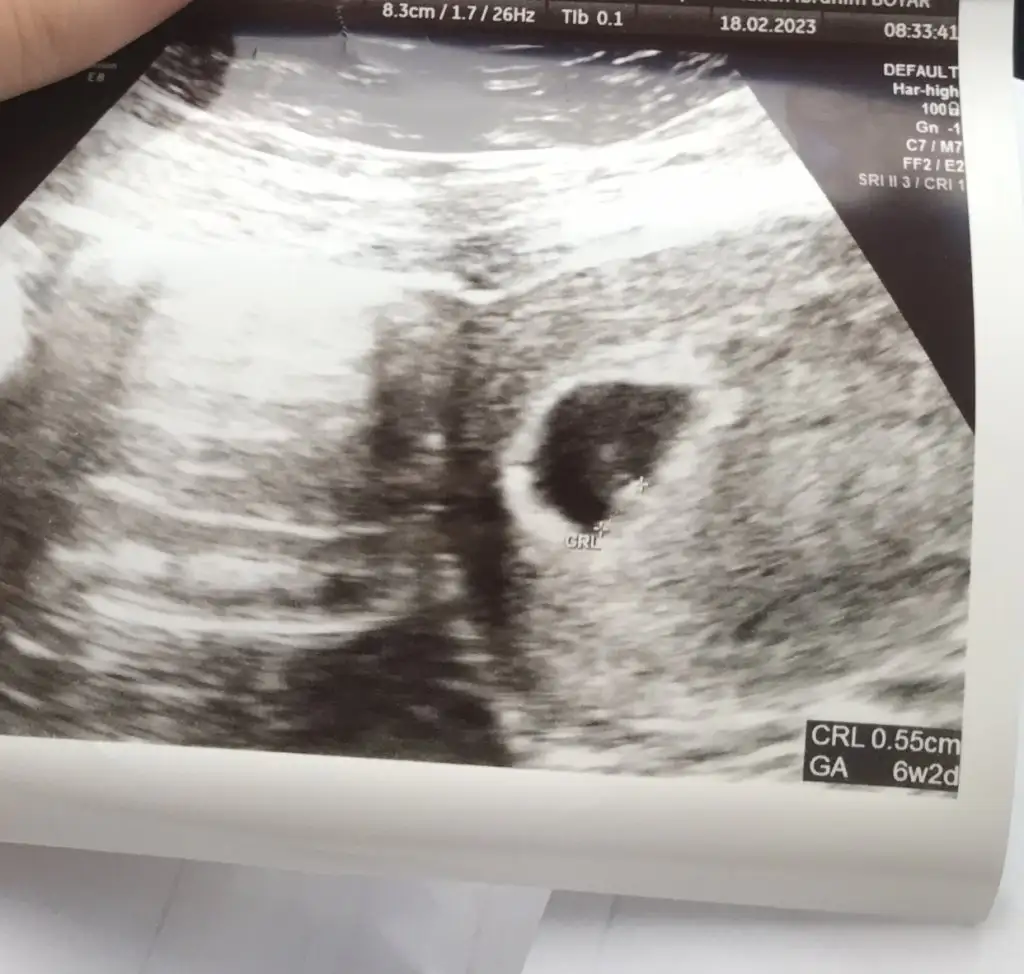

Yolk sacı gormus onu gorduyse bebek olusuyor demektır kuzum zaten halka yuzuk gıbı düşün ilk o halka olusuyor sonra tasınıda bebek dusun orda da bebek olusuyorÖyle mi diyorsunamin kuzum peki bana ultrasonda bebeği göremiyorum ama eşine benzer bir şey görüyorum dedi demek istediği acaba ne olabilir ben anlamadım açıkçası

Kesem 7.5 mm 5+5 im kuzuSenin ne kadarlık olmuştu canım

Valla yolk sac demedi acaba onu kastetti acaba bilmiyorum canım perşembe gideceğim kendi doktoruma özele inşallah görürüz minnoşuYolk sacı gormus onu gorduyse bebek olusuyor demektır kuzum zaten halka yuzuk gıbı düşün ilk o halka olusuyor sonra tasınıda bebek dusun orda da bebek olusuyor

Maşallah canım Rabbim sağlıkla kucağına almayı nasip etsin dua etmeyi unutmayın canım kaybetmeyeyim bebeğimiKesem 7.5 mm 5+5 im kuzu

Devlette tahlillerimi yaptırıp özelde muayeneye devam etmeyi düşünüyorum artık canımAyy senle evet aynı şeyi yaşamışız. Hayır bide ben özelde yolk kesesini gördüğümü söylediğim halde bebek yok diyopazartesi özele gidicem sanırım görürüm. İnsanı durduk yere üzüyolar zaten zor kavuşmuşum tüp bebek olduğunu söylediğim halde çok sert davrandı